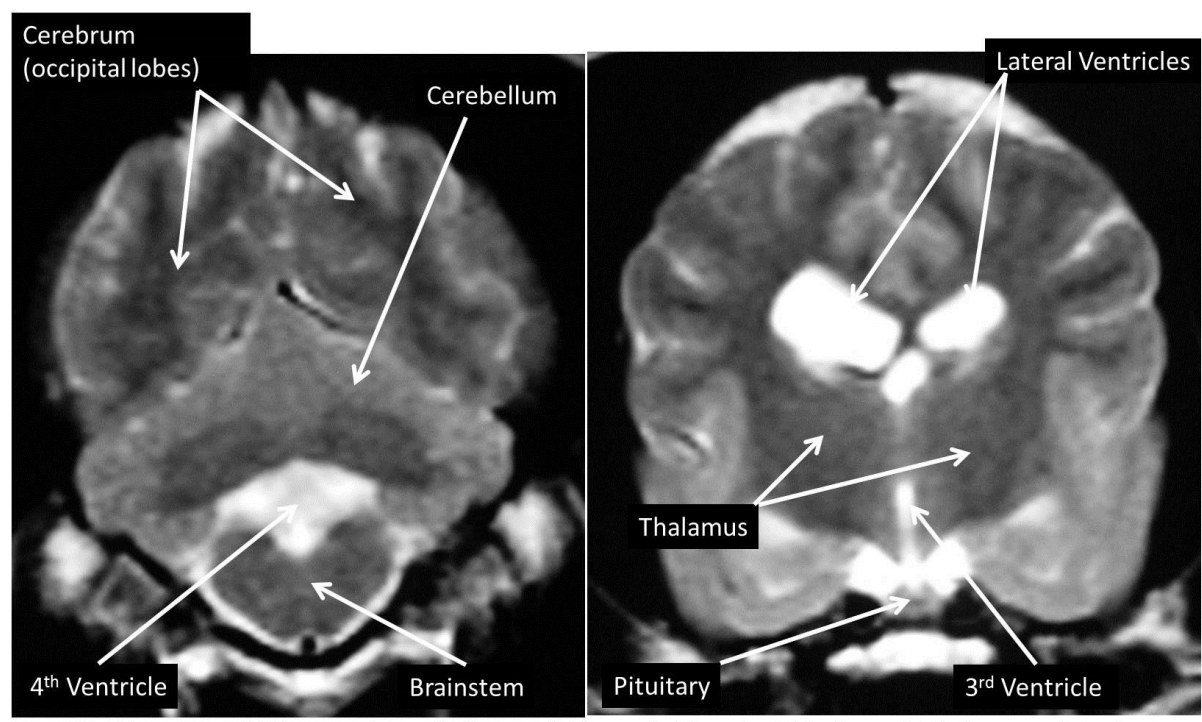

identify the lateral ventricles, pituitary, cerebellum, cerebral hemispheres, brainstem, eyeballs

how does fluid appear on T1w and T2w scans

T1w = hyperintense

T2w = hypointense